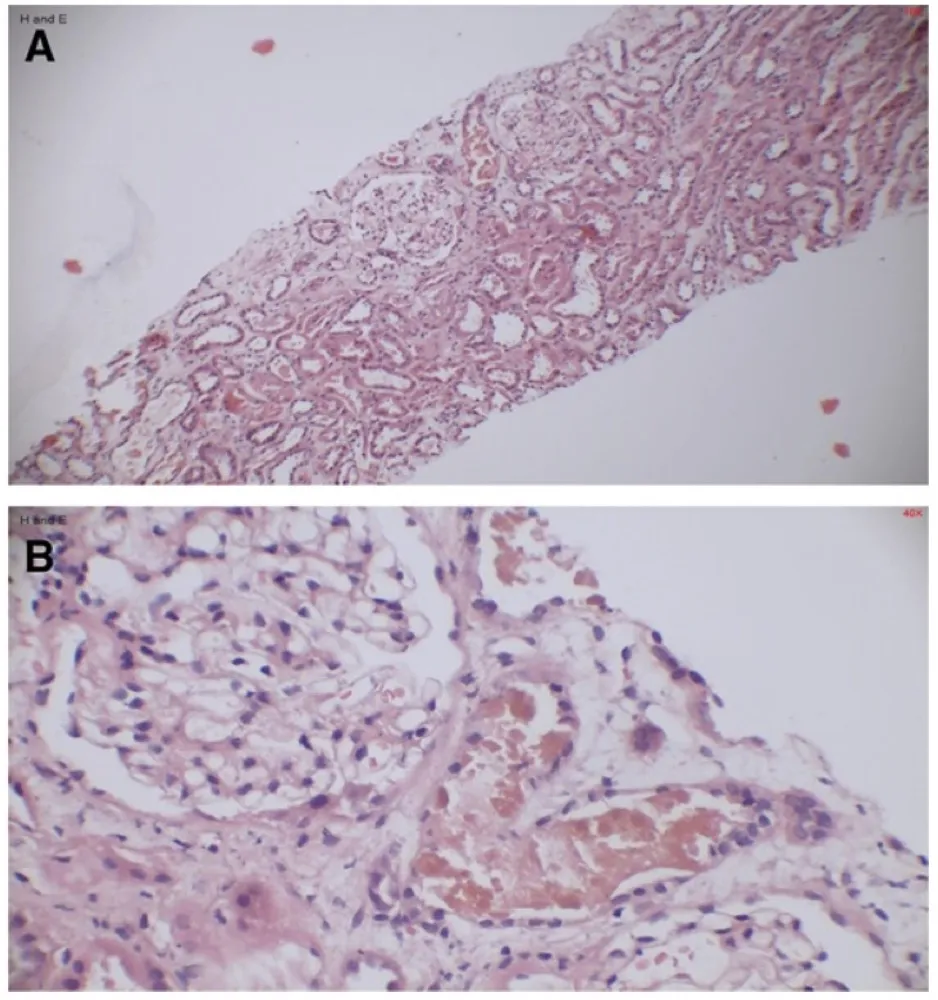

Uma causa incomum de hematúria glomerular intermitente!

Hematúria pós infecção, caso clínicos para auxiliar no entendimento de causas glomerulares comuns e raras...